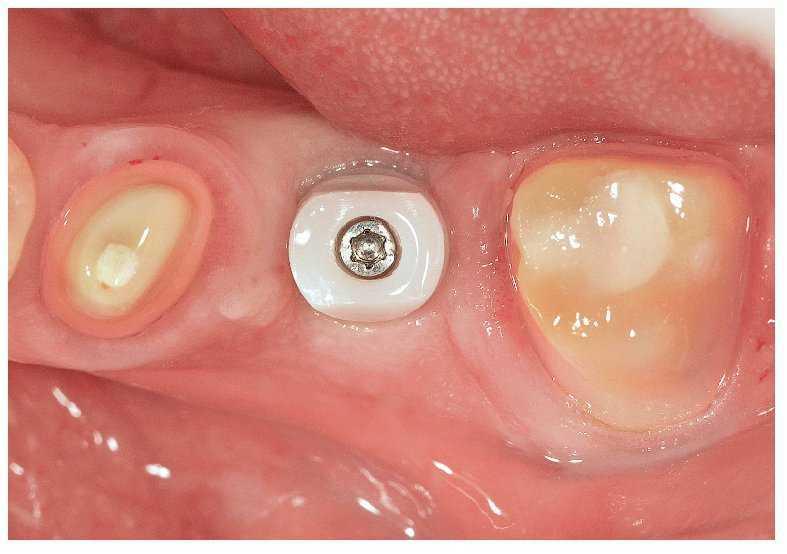

En el presente caso se orientó correctamente el implante en función de la sustancia ósea existente y de los dientes adyacentes, y en el maxilar opuesto se orientó bucolingualmente (fig. 5b). De este modo, los contornos y la función de la corona del implante se ajustan de forma óptima a lo largo del eje del implante y se evitan fuerzas laterales indeseadas4,18,52,57. Una representación tridimensional de la situación clínica, una planificación adecuada del tratamiento y una orientación correcta del implante facilitan la consecución de la meta protésica. Un implante insertado a la suficiente profundidad crea espacio para un pilar con recorrido subgingival del margen y un perfil de emergencia de la corona satisfactorio (fig. 5c).

Fig. 5b. Vista desde oclusal: el implante con cofia de cicatrización.

Fig. 5c. Vista desde oclusal: el implante sin cofia de cicatrización. La posición del implante extremadamente favorable en relación con el diente adyacente, así como el tejido blando periimplantar sano, posibilitan una toma de impresión limpia.

La impresión de los implantes pueden realizarse optativamente en cubeta abierta o cerrada. La impresión en cubeta abierta es preferible en virtud de su mayor exactitud, especialmente cuando se debe tomar la impresión de varios implantes. Una orientación mesiodistal y bucolingual correcta (fig. 5d) posibilita una configuración óptima del pilar, independientemente de si la corona está cementada o atornillada (figs. 5e a 5g).